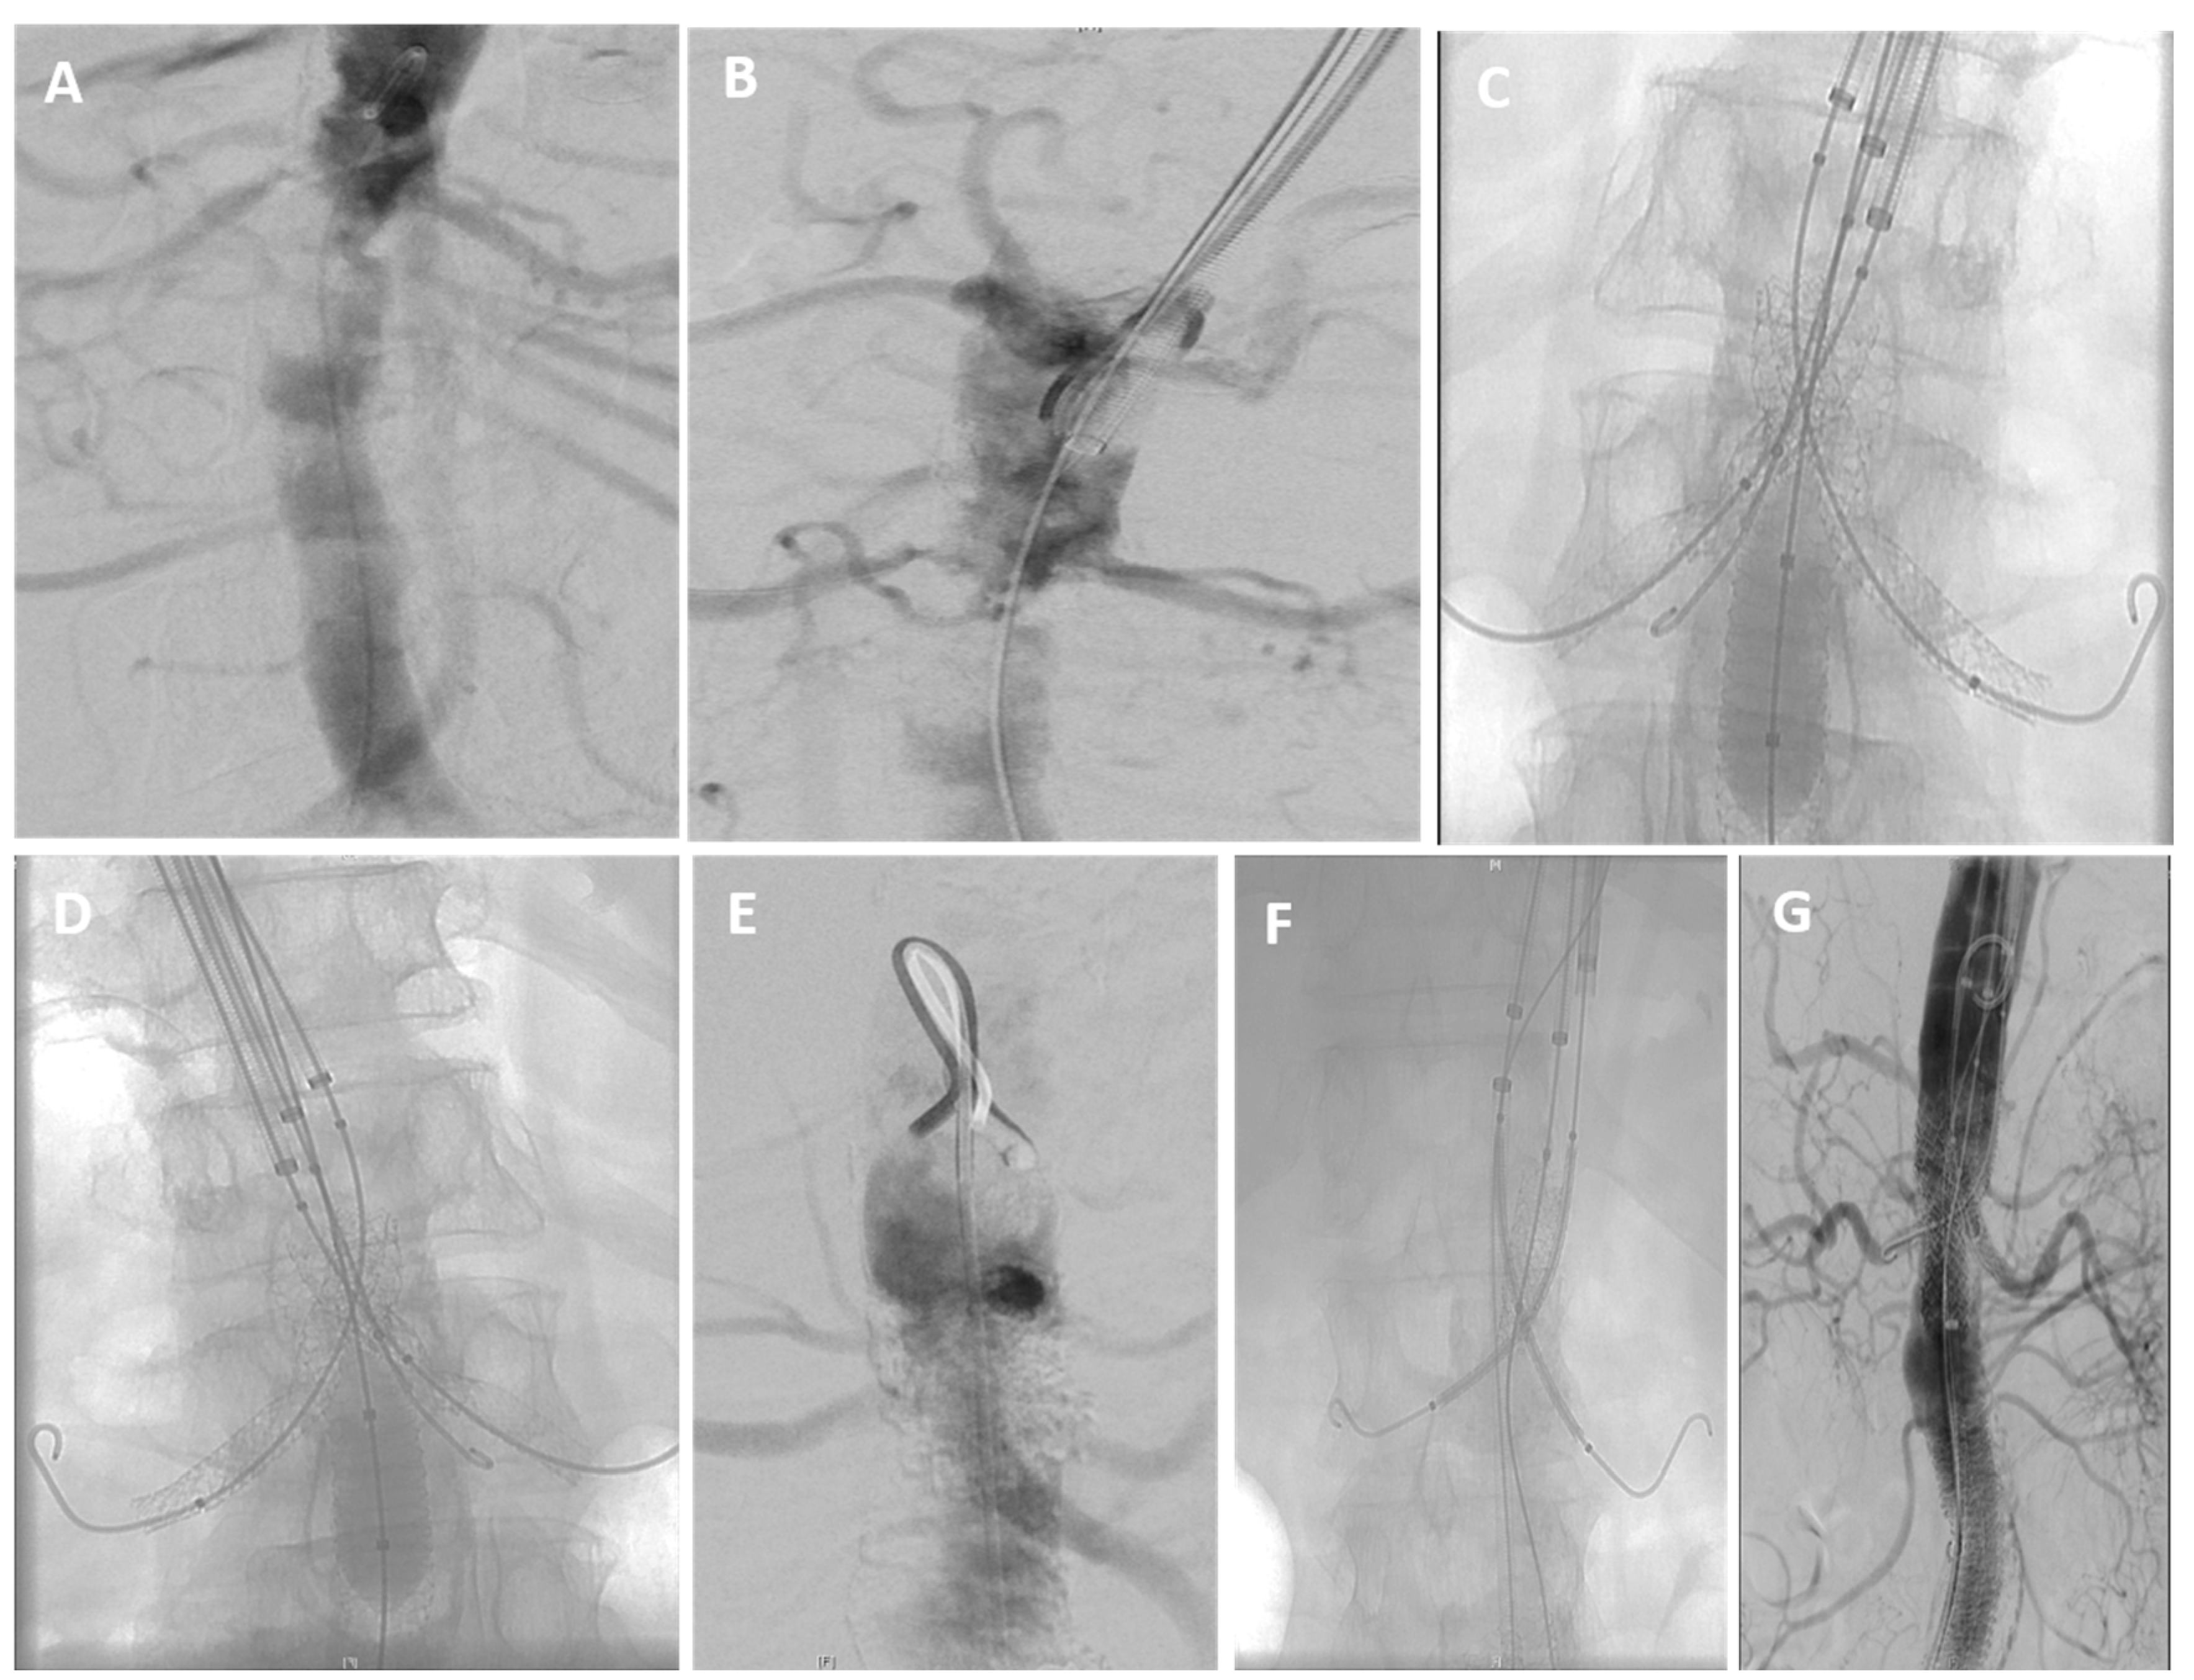

2.3. Endovascular Procedure